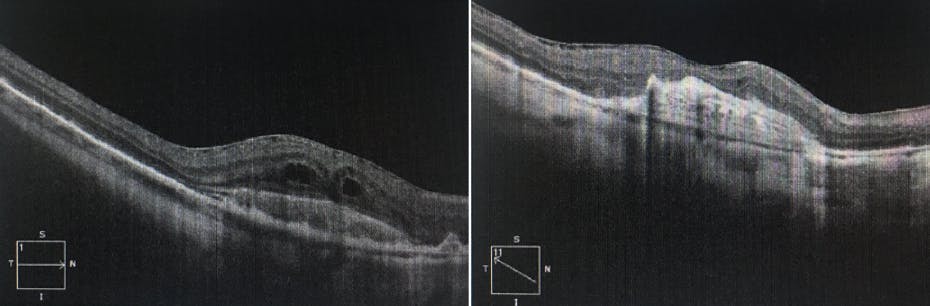

<p>Figure. This patient presented with a baseline VA of 20/200 and struggled to fixate centrally. After 9 months of monthly treatment with bevacizumab, VA improved to 20/80 with central fixation. Although the patient was not impressed with his visual improvement, VA in his other eye was counting fingers at 3 feet. Dr. Han believes he saved the vision in this patient’s good eye from becoming just as bad and preserved meaningful visual function overall for the patient.</p>

Figure. This patient presented with a baseline VA of 20/200 and struggled to fixate centrally. After 9 months of monthly treatment with bevacizumab, VA improved to 20/80 with central fixation. Although the patient was not impressed with his visual improvement, VA in his other eye was counting fingers at 3 feet. Dr. Han believes he saved the vision in this patient’s good eye from becoming just as bad and preserved meaningful visual function overall for the patient.